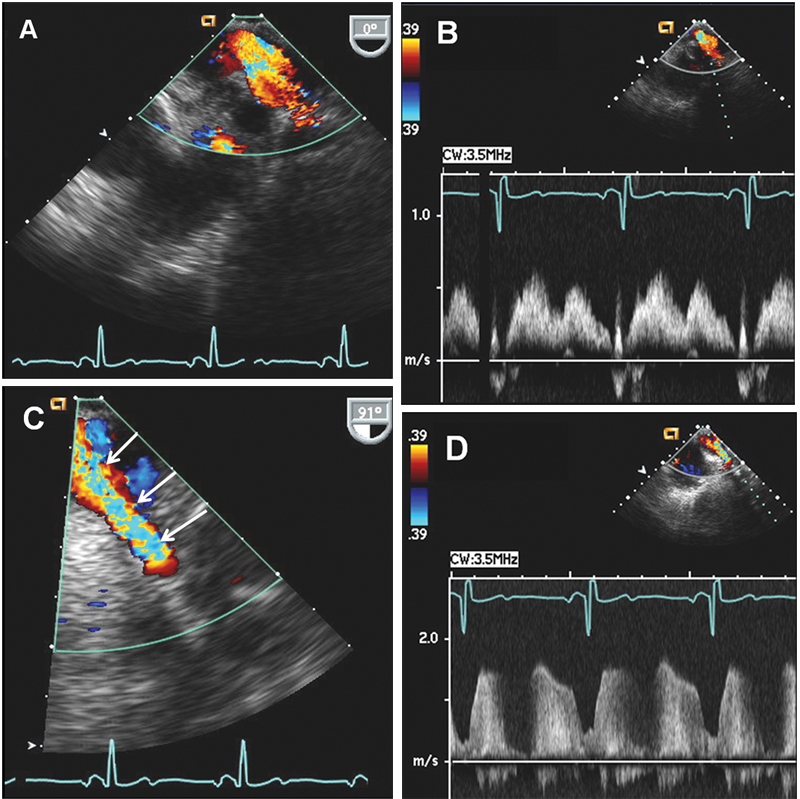

فحوصات تشخيصية لبعض امراض القلب والشرايين التاجية